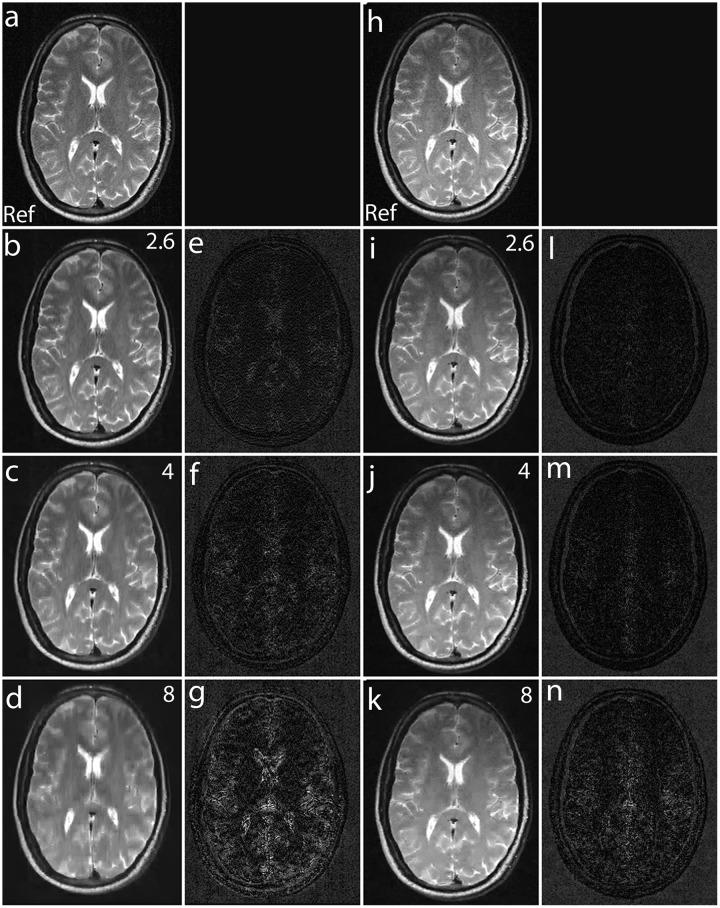

The incoherence between measurement and sparsifying transform matrices and the restricted isometry property (RIP) of measurement matrix are two of the key factors in determining the performance of compressive sensing (CS). In CS-MRI, the randomly under-sampled Fourier matrix is used as the measurement matrix and the wavelet transform is usually used as sparsifying transform matrix. However, the incoherence between the randomly under-sampled Fourier matrix and the wavelet matrix is not optimal, which can deteriorate the performance of CS-MRI. Using the mathematical result that noiselets are maximally incoherent with wavelets, this paper introduces the noiselet unitary bases as the measurement matrix to improve the incoherence and RIP in CS-MRI. Based on an empirical RIP analysis that compares the multichannel noiselet and multichannel Fourier measurement matrices in CS-MRI, we propose a multichannel compressive sensing (MCS) framework to take the advantage of multichannel data acquisition used in MRI scanners. Simulations are presented in the MCS framework to compare the performance of noiselet encoding reconstructions and Fourier encoding reconstructions at different acceleration factors. The comparisons indicate that multichannel noiselet measurement matrix has better RIP than that of its Fourier counterpart, and that noiselet encoded MCS-MRI outperforms Fourier encoded MCS-MRI in preserving image resolution and can achieve higher acceleration factors. To demonstrate the feasibility of the proposed noiselet encoding scheme, a pulse sequences with tailored spatially selective RF excitation pulses was designed and implemented on a 3T scanner to acquire the data in the noiselet domain from a phantom and a human brain. The results indicate that noislet encoding preserves image resolution better than Fouirer encoding.

测量矩阵与稀疏变换矩阵之间的非相干性以及测量矩阵的受限等距特性(RIP)是决定压缩感知(CS)性能的两个关键因素。在CS-MRI中,随机欠采样的傅里叶矩阵被用作测量矩阵,小波变换通常被用作稀疏变换矩阵。然而,随机欠采样的傅里叶矩阵与小波矩阵之间的非相干性并非最优,这会降低CS-MRI的性能。利用噪声小波与小波具有最大非相干性这一数学结果,本文引入噪声小波酉基作为测量矩阵,以改善CS-MRI中的非相干性和RIP。基于一项经验性RIP分析,该分析比较了CS-MRI中的多通道噪声小波和多通道傅里叶测量矩阵,我们提出了一种多通道压缩感知(MCS)框架,以利用MRI扫描仪中使用的多通道数据采集的优势。在MCS框架中进行了模拟,以比较不同加速因子下噪声小波编码重建和傅里叶编码重建的性能。比较结果表明,多通道噪声小波测量矩阵的RIP比其傅里叶对应矩阵更好,并且噪声小波编码的MCS-MRI在保留图像分辨率方面优于傅里叶编码的MCS-MRI,并且可以实现更高的加速因子。为了证明所提出的噪声小波编码方案的可行性,设计并在3T扫描仪上实现了一种具有定制空间选择性射频激发脉冲的脉冲序列,以从体模和人脑获取噪声小波域中的数据。结果表明,噪声小波编码比傅里叶编码更好地保留了图像分辨率。